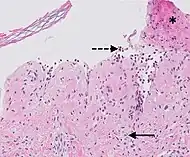

| Prevesicular stage of bullous pemphigoid | Image at right shows influx of inflammatory cells including eosinophils and neutrophils in the dermis (solid arrow) and blister cavity (dashed arrows), and deposition of fibrin (asterisks).[15] However, the diagnosis of bullous pemphigoid consist of at least 2 positive results out of 3 criteria:[19]

|

![]() |